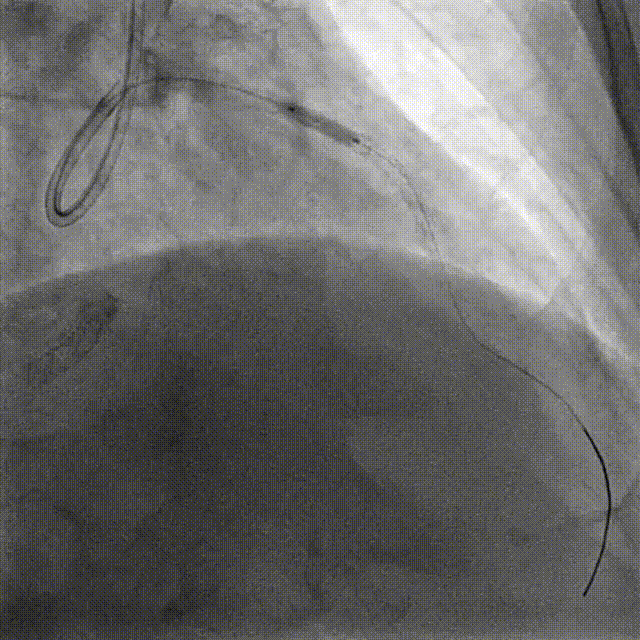

DES Deployment & Optimization DES 4.0*20mm → NC 4.0*12mm @ 20atm

Final Results